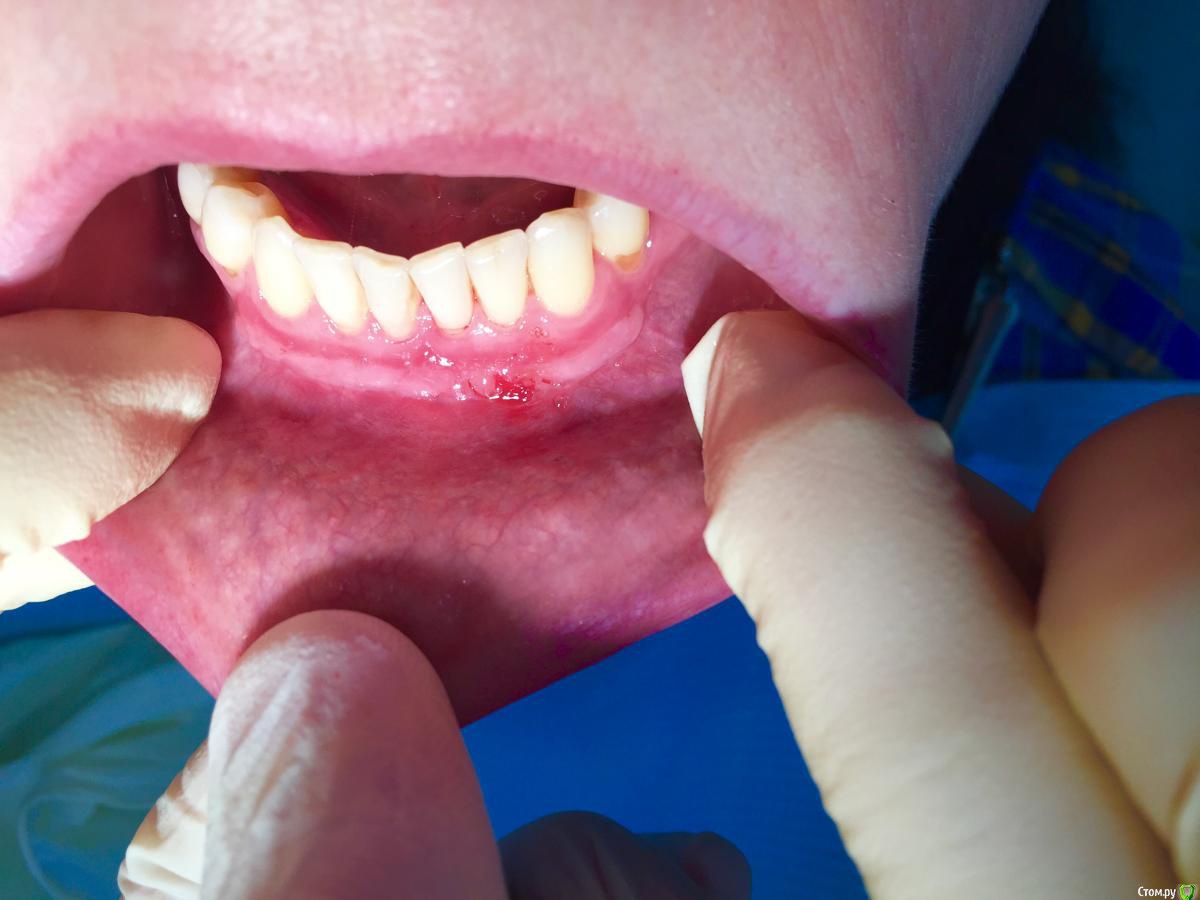

Dr.Safiullin Опубликовано 12 мая, 2017 Поделиться Опубликовано 12 мая, 2017 (изменено) Добрый вечер всем, решил тоже свой первый, небольшой кейс выложитьСильно не ругайте, полгода как получил диплом) Вопрос: 1)Нужно ли подшивать губу? Я не подшил, потому что в гос. времени мало на приём, да и испугался надкостницу травмировать лишний раз. А то боялся получить рубец, хотя не получил его!) 2) на 5 фотке это десквамация? Приветствуются конструктивная критика! Спасибо Изменено 12 мая, 2017 пользователем Dr.Safiullin Ссылка на комментарий

Dr.Safiullin Опубликовано 13 мая, 2017 Автор Поделиться Опубликовано 13 мая, 2017 Доктор, вы прекрасно провели ненужную и бесполезную операцию )) Тут не было показаний для вестибулопластики.Может быть, но а как же преддверие 1.5-2мм, тонкий биотип десны, рецессия по 3 классу по Миллеру в области фронтальных зубов? Из за скученность тоже убыль, но все же. Вот тут может быть информативнее будет Ссылка на комментарий